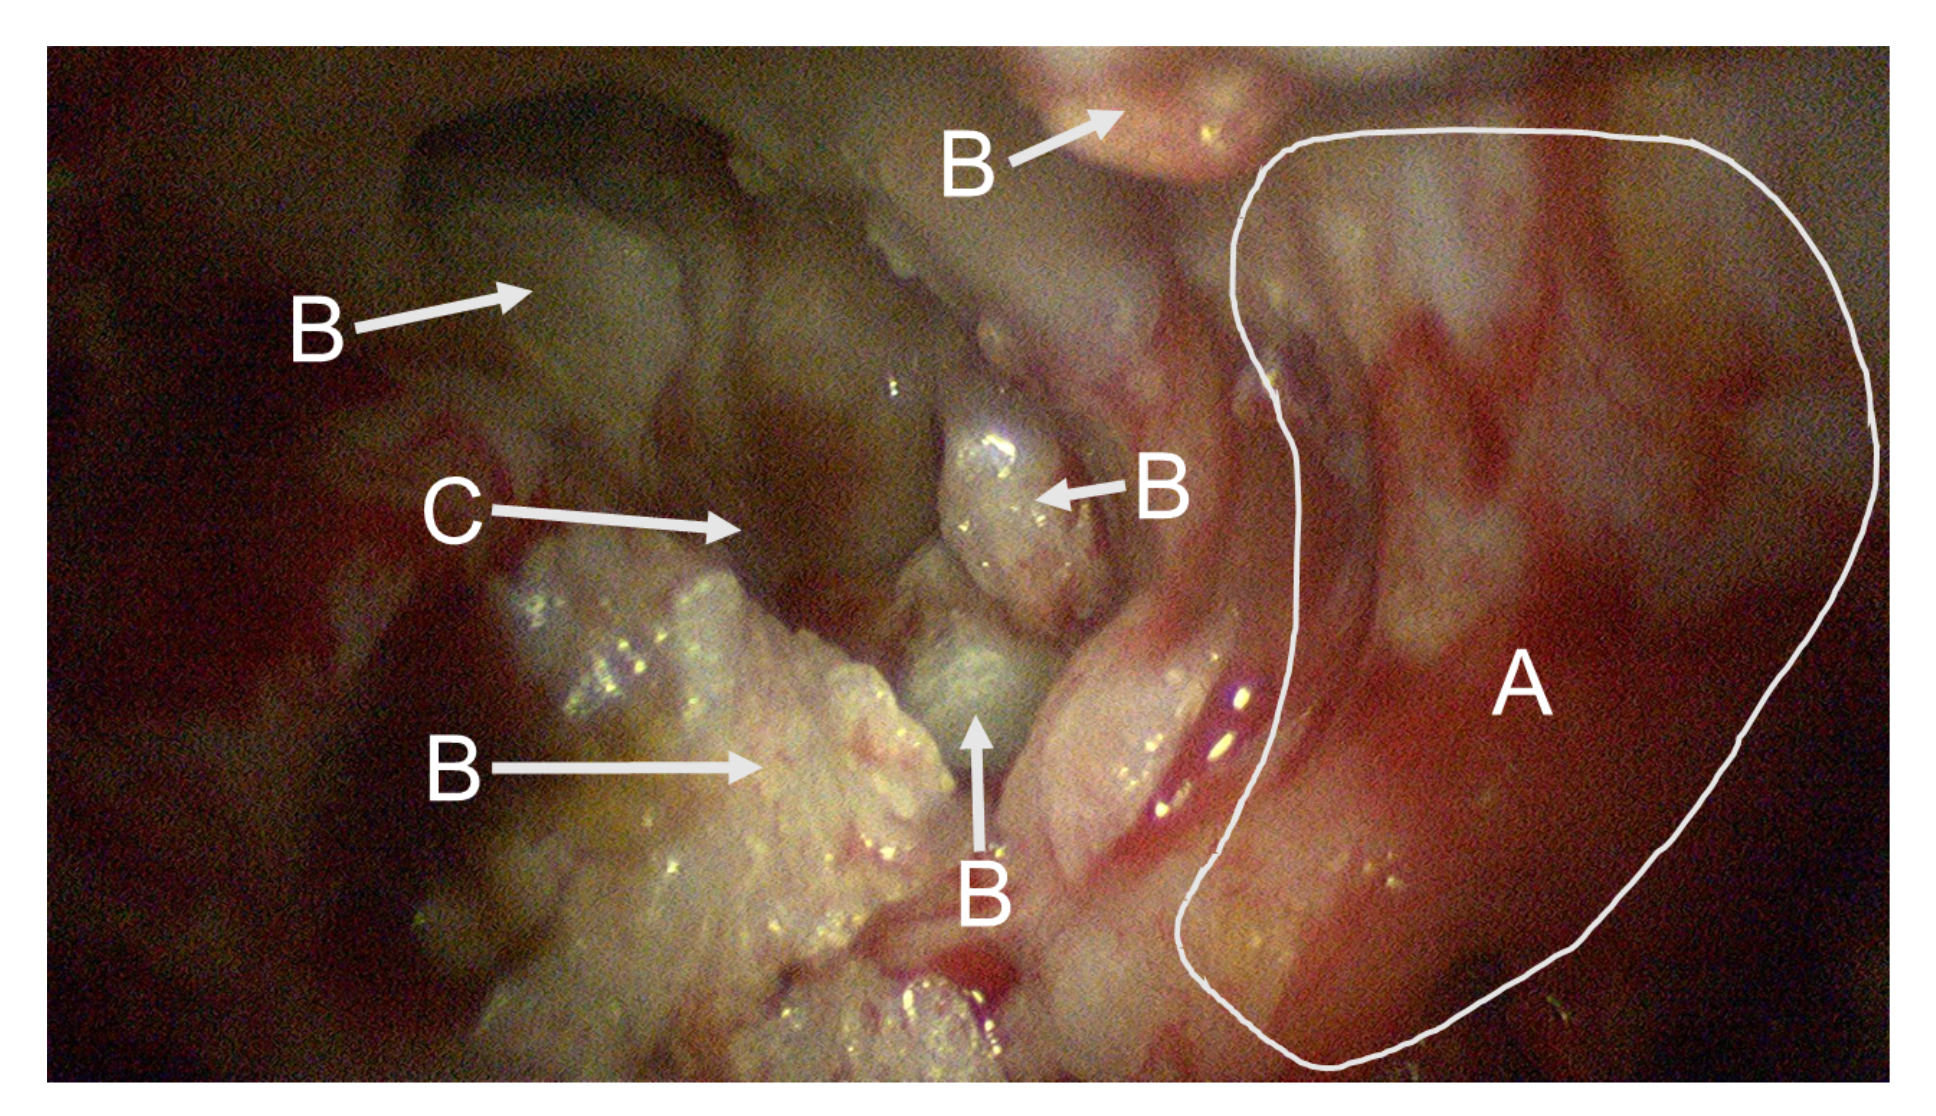

3.2. Cholesteatoma Visualization